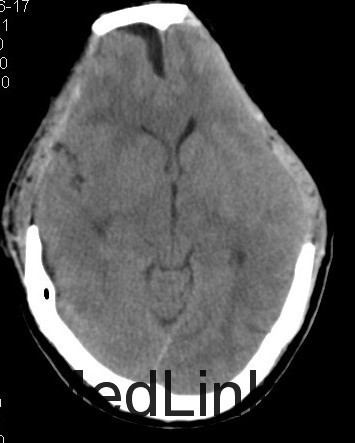

主诉:头部外伤7小时 病史:患者于7小时余前不慎从2米高处坠落,头部着地,并昏迷,左侧外耳道出血,无呕吐,无肢体抽搐,无明显头晕及头痛,无胸闷心悸,呼120入我院急诊诊治,行头颅CT提示有:头部螺旋CT平扫:1、蛛网膜下腔出血;大脑镰硬膜下出血;双侧额叶脑挫伤;脑肿胀。2、左侧枕骨骨折;左侧顶枕部头皮下血肿。3、双侧筛窦炎症。入急诊后患者神志转清,在急诊给予止血、脱水等治疗,4小时后复查头颅CT提示血肿增大及挫裂伤较前明显加重,为进一步治疗,收入我科。患者起病前,精神食欲可,二便可,体重无明显变化。

查体:神志昏睡,间断烦躁,刺激可睁眼,无对答,查体不合作,双侧瞳孔等大等圆,直径3mm,对光反应尚可,枕部可见隐约血肿,约1*1cm,左耳见血性液体流出。深浅感觉查体及腱反射查体不合作,双侧病理征未引出。格拉斯哥评分9分。 4:辅助检查:头部螺旋CT平扫(套:1、蛛网膜下腔出血;大脑镰硬膜下出血;双侧额叶脑挫伤;脑肿胀。2、左侧枕骨骨折;左侧顶枕部头皮下血肿。3、双侧筛窦炎症。颈椎螺旋CT平扫+三维:寰椎与枢椎齿状突之间高密度影,考虑撕脱骨折与钙化灶鉴别,建议复查或MRI进一步检查。

诊断:1、双侧额挫裂伤; 2、大脑镰、右侧额颞硬膜下出血;3、右额颞脑出血; 4、左枕骨骨折; 5、中枢神经系统感染 主要经过:入院后完善术前相关检查,行右侧额颞脑挫裂伤清除+去骨瓣减压+颅内压探头置入术;后行左侧额叶血肿清除+额颞顶去骨瓣减压术,术后予以抗感染、营养神经、改善循环、化痰、护胃、抗癫痫及营养支持治疗。 术后复查CT:双侧额颞顶骨局部缺如;左侧枕骨不连。 双侧额颞顶部皮下软组织稍肿胀。双侧额叶软化灶;右侧额颞部硬膜下及大脑纵裂池积液;右侧额颞部少量积气